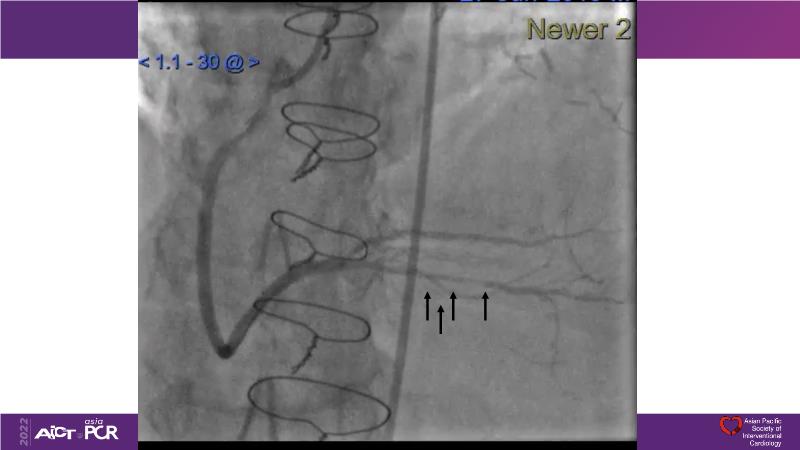

Consult this session to understand the technology and scientific evidence of the novel sirolimus drug-coated balloon, to learn its utility for PCI in a variety of lesion and patient subsets and to understand the evidence and outcomes in real-world patients.

- To understand the technology and scientific evidence of the novel sirolimus drug-coated balloon (SDCB)

- To learn the utility of the DCB for PCI in a variety of lesion and patient subsets

- To understand the evidence and outcomes of this DCB in real world patients